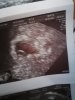

A tam w rogu już na końcu badania zauważyła ciałko żółte

• IMG_20200818_140745.jpg

W 6 tyg... Dzisiaj jest równe 6tyd od ostatniej miesiączki... W tej straconej zarodek był 5tydz 5d

To ja miałam badanie gdzie wykazało tylko puste jajo w 6+3 od ostatniej miesiączki i moje jajo nie miało tak ładnej plamki jak twoje, faktycznie wyglądało tylko na puste. A już brałam luteinę 200 i nadal biorę raz na noc.

A mam pytanko mówiłaś ze bylas u Gina przed okresem a wiesz jaki mialas poziom beta? I co widziałaś na 1 usg? :)